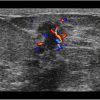

Ung thư vú

Ung thư vú - Ảnh 2

» Thông tin: Nữ giới – 59 tuổi.

» Lâm sàng: Khối tuyến vú.